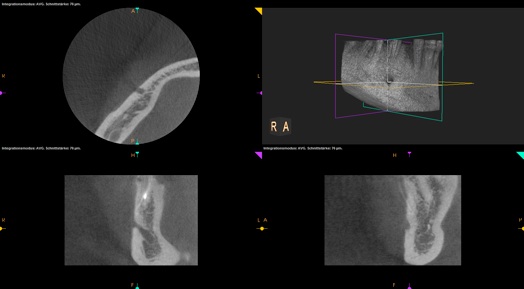

Im Vergleich zur herkömmlichen Röntgentechnik mit Film, ist beim digitalen Röntgen die Strahlendosis deutlich reduziert. Die Röntgen-bilder werden mit hochsensiblen Sensoren aufgenommen und stehen sofort zur Auswertung auf dem Computerbildschirm am Behand-lungsplatz bereit.